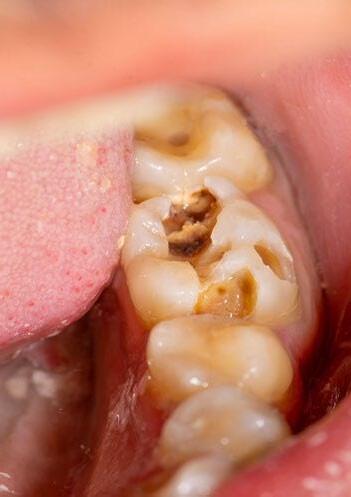

DISADVANTAGE STARTS EARLY: ORAL HEALTH CHALLENGES IN ENGLISH ACADEMY FOOTBALLERS

This article summarises key findings from recent research published in BMJ Open Sport & Exercise Medicine by Konviser et al. (2025).1 The study examined the oral health of 160 academy football players from 10 English clubs, highlighting an early onset of oral disease and its potential impact on player wellbeing and performance. The findings raise critical questions for the wider football medicine community.

sporting performance capacity,2-8 with previous research into professional footballers in the UK showing high levels of untreated dental caries, gum disease and a perceived negative performance impact.9 The study by Konviser et al. (2025)1 reported that these issues were already present in football academies.

Among participants, 76.8% presented with gingivitis (gum inflammation), 22.5% with periodontitis (irreversible gum disease), and 31.2% with dental caries requiring treatment. Screening for dental trauma revealed that 35.6% had

sustained trauma to their incisor teeth, while 15.5% showed evidence of severe tooth wear. Notably, one in ten players reported missing training sessions due to oral health problems.

Teeth

The largest representative sample of footballers by UCL2 found that 37% of players had active dental caries (decay) and 53% had dental erosion (loss of enamel or dentine).

A very recent study of academy players identified high levels of oral disease: 31.2% had dental caries requiring treatment; 76.8% had gingivitis; and 22.5% had periodontitis. Tooth wear affecting up to at least 50% of tooth structure was present in 15.5% of participants.15

Dental decay will cause pain and often players learn to chew differently, avoiding certain triggers and this can affect nutrition intake. Dental erosion can cause sensitivity which can be disruptive. Both can contribute to poor sleep.3